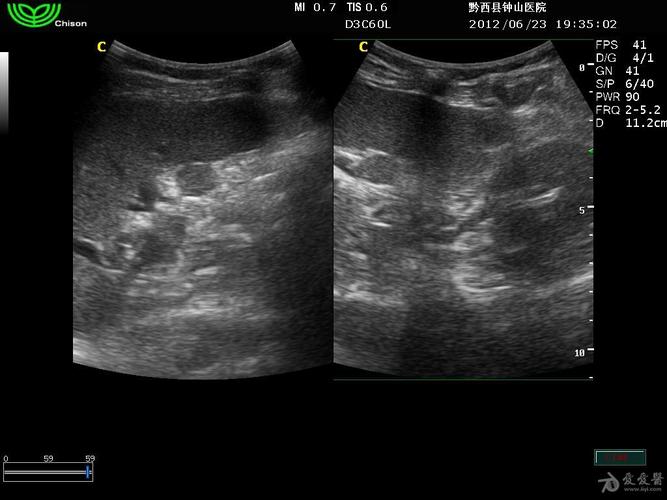

请看看这是副脾吗 - 超声医学讨论版 - 爱爱医医学论坛 - 爱爱医医学

副脾超声图片

副脾彩超图片